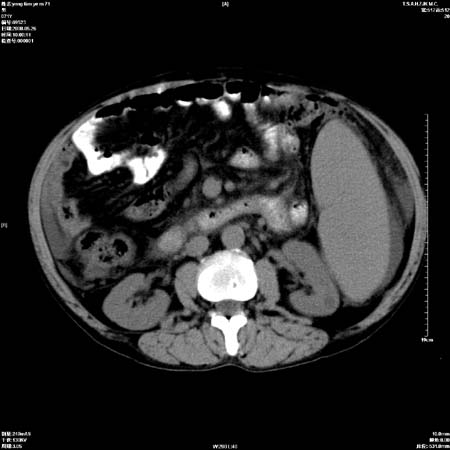

以下是引用医影拾贝在2008-6-5 22:48:00的发言:[br]肝硬化、门脉高压、胃底食管静脉曲张、低蛋白血症(胆囊壁水肿、增厚)、腹水[br]脾功能亢进、脾大、脾、左肾囊肿[br]肝囊性占位、不除外肝脓肿可能[br]建议增强以除外肝右叶肝ca可能

以下是引用chenglinhunan在2008-6-5 22:53:00的发言:[br]1. 肝硬化腹水,脾肿大。[br]2. 肝右后叶占位,肝癌。[br]3。建议ct增强扫描。

以下是引用zjzjr在2008-6-6 12:34:00的发言:[br]1. 肝硬化腹水,脾肿大。[br]2. 肝右后叶占位,肝癌。[br]3。建议ct增强扫描。[br]4肝脾囊肿.